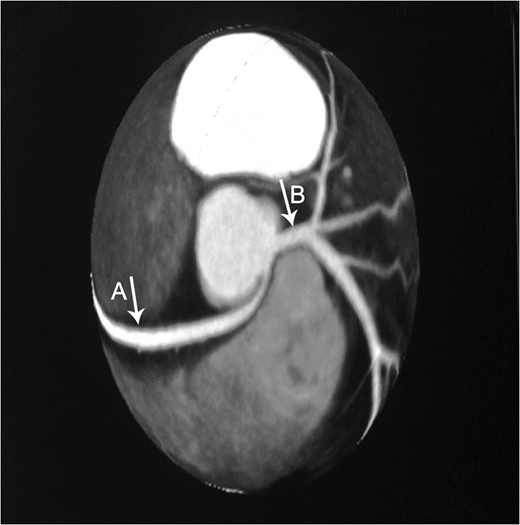

Constructional CT demonstrates an anomalous origin of RCA (Arrow A) which arises as a branch from LMCA (Arrow B).

This previously asymptomatic 37-year-old patient presented with continuous complaints of dyspnea on exertion associated with chest pain. Making her candidate for CTA which demonstrated the very rare anomalous origin of the RCA as a proximal branch from the LMCA that then continues between the pulmonary artery and ascending aorta where it is slightly compressed during systole. This finding provides us with the explanation of the presenting symptoms of such a case, which is supported by Grollman et al. ateriographic study [5].